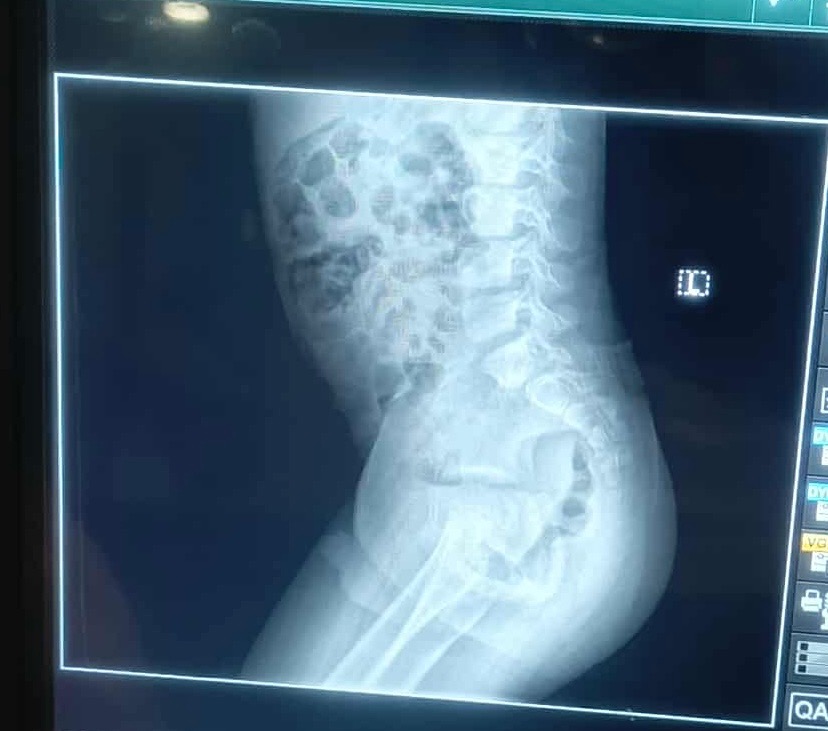

Hi to all my family and friends, I have started a fundraising page to help my 10-year-old nephew in Liberia who is hospitalized from a fall. He has injuries that have him in so much pain. From what I see from the X-ray, it looks like his spine and hips were moved. My sister took him to the hospital, but they are refusing to treat him without money. They were able to do an X-ray with the little money I had, but they can't do anything else without payment upfront. It's heartbreaking as a mother of 5 to watch my nephew sit in the hospital's uncomfortable bed, crying and screaming in pain with no treatment as his voice echoes through the building. Please help him; even a prayer or anything will be helpful. Please, I can't imagine losing another family member.

Update: I had to change the amount because my nephew needs surgery as his spine is broken his belly is swollen and he can’t feel his lower body. We have to transfer him to a better hospital that can help him with the surgery, but it’s expensive they won’t help him with out the money. Please family and friends I appreciate everything as I’m in tears right now I don’t know how to thank you let god bless you for your help and support.